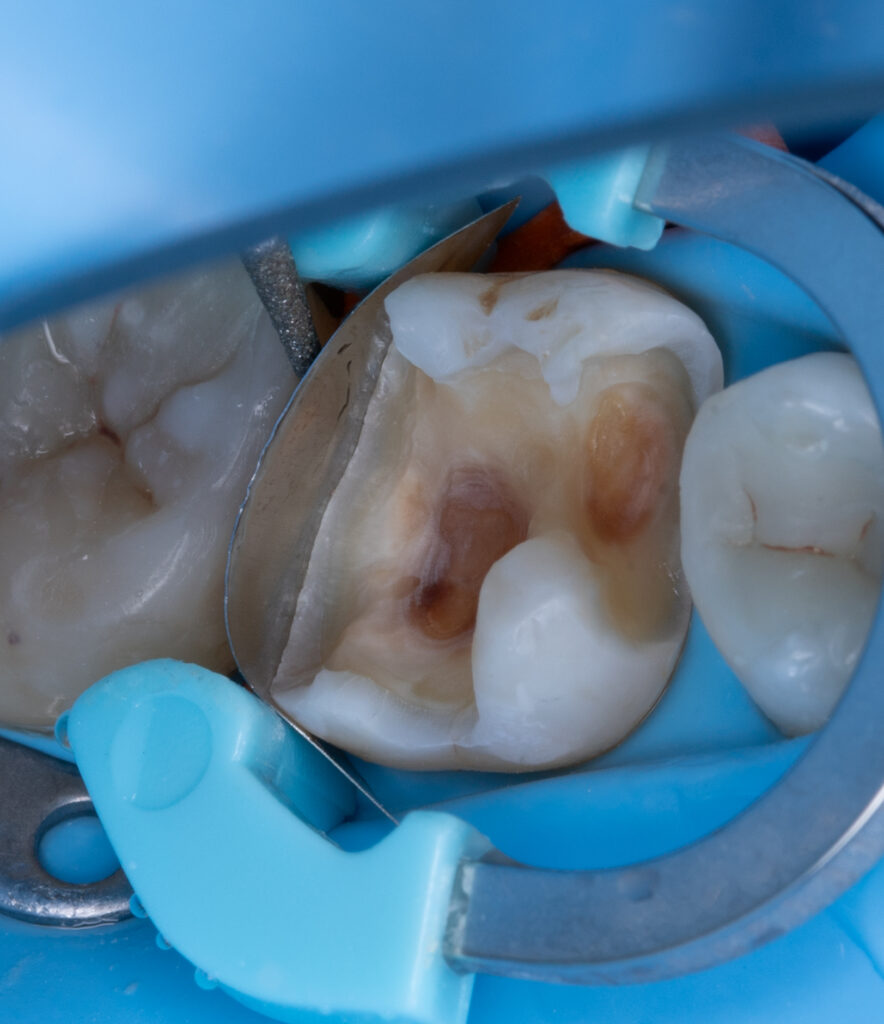

At the beginning of the treatment of deep caries on tooth 2.6, a pulp vitality (friz) test and a periapical radiograph were performed before anesthesia to confirm that the tooth was vital. Necrotomy was then carried out using a white diamond round bur and a bur on the contra-angle handpiece down to sound dentin. All infected dentin (KID) was completely removed, while cariously affected dentin (CAD) was preserved if it was hard and pigmented.

Wooden wedges and a Palodent matrix system were applied to ensure proper embrasure and facilitate proximal wall restoration. The proximal walls were rebuilt using Asteria A2B composite, and EverX Bulk Fill was placed inside the tooth to reduce stress, minimizing the C-factor and polymerization stress. The tooth anatomy was subsequently restored with NeoSpectra in shades A2 and D1, and the fissures were stained with Mecherium Color Brown.